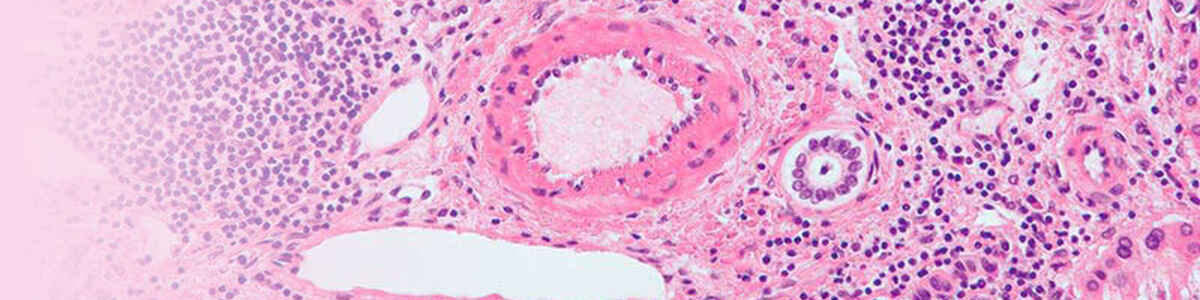

Nghiên cứu lâm sàng

Khám phá Nghiên cứu lâm sàng cách Nikon có thể hỗ trợ bạn trong việc phát triển các phương pháp điều trị và chẩn đoán mới.